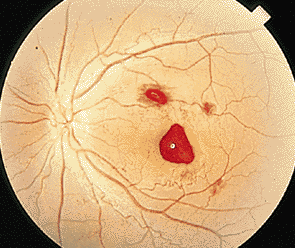

很多人常常感覺到看東西越來越模糊,并且眼前常常有黑點(diǎn)在慢慢的移動。即使你不斷的閉上眼睛,用淚水洗盡眼睛表面,眼睛視力依舊模糊。這極有可能眼睛的玻璃體位置出現(xiàn)問題了。這在眼科上也被稱為玻璃體變性,人的眼睛玻璃體它是一種由II型膠原纖維網(wǎng)支架和其中的透明質(zhì)酸分子構(gòu)成特殊的粘液性膠樣組織,它本身沒有血管,所以新陳代謝及其緩慢。”正常的玻璃體是一種無色透明膠狀體,它具有屈光和固定視網(wǎng)膜的作用,使得外界物象能夠精確的投射在眼底黃斑上。一般的玻璃體變性患者,表現(xiàn)為玻璃體液化、后脫離、或者萎縮導(dǎo)致混濁。

對于很多患者而言,玻璃體變性主要原因就是隨著年齡不斷增加,新陳代謝不斷變緩,使得玻璃體自身變性。比如像星狀玻璃體變性,常常見于50歲以上,不過它只是引起視力的不適,并不會導(dǎo)致視力下降。因?yàn)椴Aw內(nèi)新陳代謝緩慢,而出現(xiàn)了含鈣的脂質(zhì)白色小球。而玻璃體變性中更為嚴(yán)重的是出現(xiàn)液化現(xiàn)象,特別是閃輝性玻璃體液化,由于嚴(yán)重眼外傷和手術(shù)后眼內(nèi)出血導(dǎo)致的玻璃體或前房會出現(xiàn)無數(shù)黃白色和其他顏色的膽固醇結(jié)晶。

對于玻璃體混濁這樣復(fù)雜的癥狀,一般的眼科醫(yī)院無法根治,由于眼睛玻璃體的特殊性,目前尚無有玻璃體變性的特效藥,只能經(jīng)過長期的治療和鞏固,使得玻璃體不會出現(xiàn)其他病變。所以對于病情較為嚴(yán)重的玻璃體變性患者而言,就像因?yàn)樽冃砸l(fā)的視網(wǎng)膜剝離或玻璃體出血等等,這些會出現(xiàn)視力嚴(yán)重減退,眼睛發(fā)紅、疼痛、畏光等等,一定要到專業(yè)的眼科醫(yī)院進(jìn)行醫(yī)治,比如在廈門眼科醫(yī)院的眼底專科,常年來除了眼底病之外,玻璃體變性治療領(lǐng)域在全國也是處于領(lǐng)先位置。